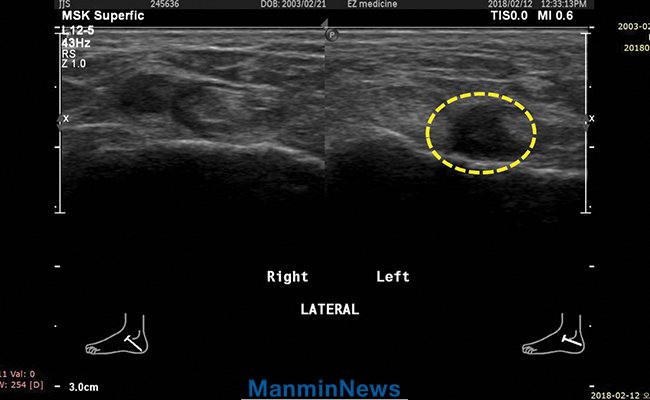

超声波照片

祷告接受前:见左腿踝关节韧带拉伤

证道结束后,接受堂会长的医治祷告时,感觉有外力托住我受伤的左脚踝,使得内部组织逐一有序地连接。为了解状态如何,12日(周一)去医院看伤,诊断是“左侧足关节韧带拉伤”。这种情况大多须做手术治疗,但我决意要靠神蒙医,只是为固定脚腕打了石膏。